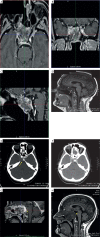

Epithelioid haemangioendothelioma (EHE) is a rare low-grade vascular neoplasm that is composed of mostly epithelioid cells. EHE may arise as a solitary tumour or in the form of multiple body lesions, and commonly occurs in soft tissues, liver, pleura, lung, peritoneum, lymph nodes, breast, and many other sites. EHE in the cranionasal region is extremely rare. There are very few reports of cases of skull-base EHE. We discuss an extremely rare presentation of an aggressive EHE that originated from the sellar region. Based on literature review, our patient is the first reported case of a giant solitary EHE with prepontine cistern invasion and abducens nerve encroachment mimicking a chondrosarcoma. We treated this rare tumour by near subtotal surgical excision with subsequent radiotherapy, considering that complete tumour resection with free margins in both cavernous sinus and clival region avoiding neural and vascular structure encroachment becomes technically difficult.